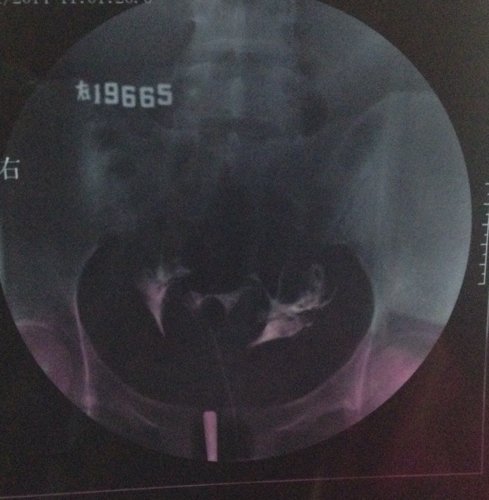

上个月输卵管造影的结果,这个月想试孕又发现卵泡没排出来,现在纠结要不要打促排卵针,片子上看起来严重 上个月输卵管造影的结果,这个月想试孕又发现卵泡没排出来,现在纠结要不要打促排卵针,片子上看起来严重吗?这个月是右卵巢有优势卵泡。医生帮忙看下,我这情况能打促排卵针吗? 点击展开 匿名用户 2014-05-11 00:08 为您推荐: 其他回答 病情分析: 你好,应该予以手术治疗的 指导意见: 可以考虑腹腔镜手术来治疗,术后注意不可过早恢复同房,及时复查。 独水凡_xjeq 2014-05-11 10:34 相关问题 3月做的输卵管造影,两侧通而欠畅,4月做卵泡监测,发现卵泡大了不排,5月刚打了促排卵针,请问我宫外 之前做造影,结果是左侧通,右侧不通,后来做输卵管通液通了,现在右侧卵泡2 1请 请问:(南京鼓楼医院)做(生殖激素测定+基础卵泡检查)跟(子宫输卵管浀造影)跟(甲功三项)大概